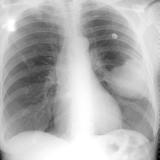

Mets

Album: Mets

Date: 02/18/2006

Size: 52 items

Views: 40293